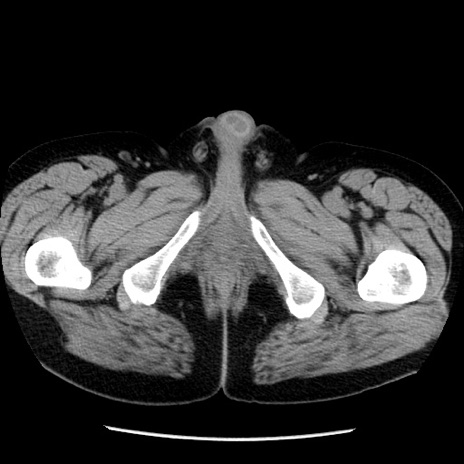

症例29(横断像)

【症例】40歳代男性

【現病歴】2日前から胃痛あり。徐々に周期的な激痛に変化した。本日になっても激痛があるため受診。

【身体所見】意識清明、BT 38-39℃台あり、腹部:膨満、やや硬、右下腹部に圧痛あり。

【データ】WBC 8500、CRP 23.26